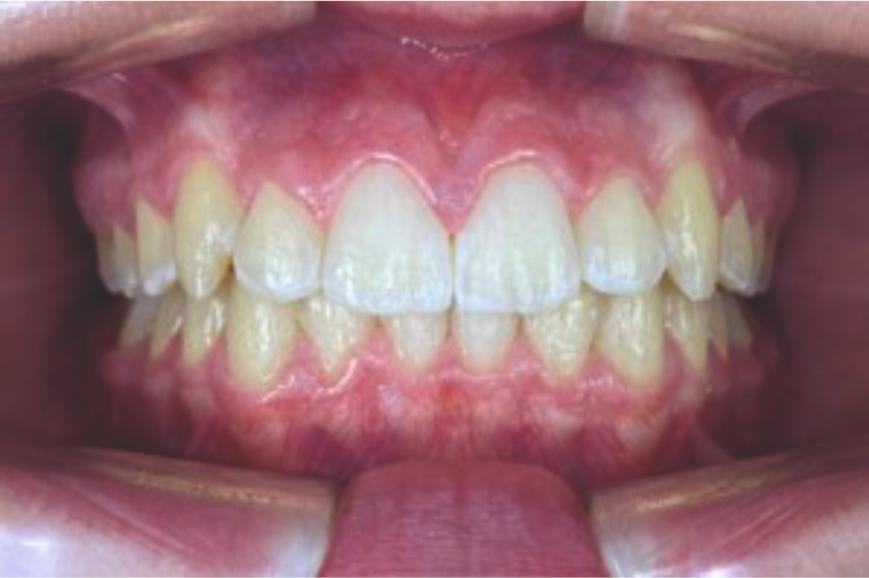

This case, led by Dr. Dalia Latkauskiene, presents the treatment of a 25-year-old female patient with a Class II division 1 malocclusion. Using the Angel Aligner PRO system with dual-modality mechanics, the treatment achieved derotation of molars, midline correction, open-bite closure, and Class I settling. In just 12 months and 40 aligners, the approach delivered precise control, enhanced function, and a significantly improved smile.